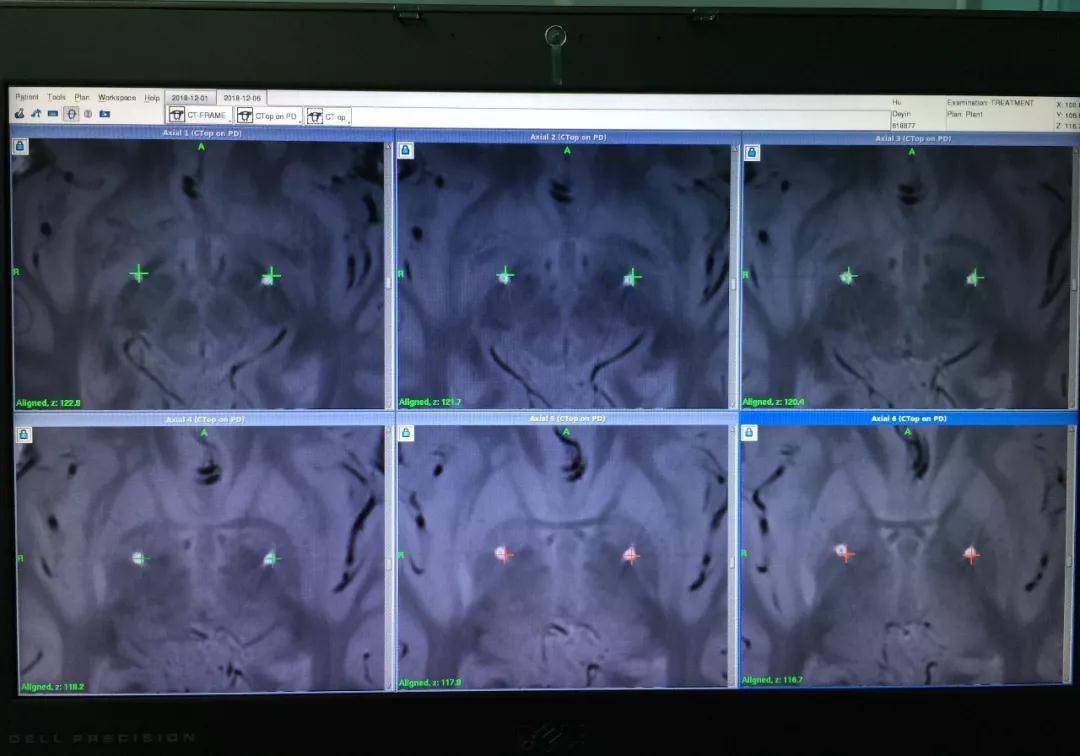

双侧颅内电极植入后,患者带框架接受CT扫描

术中CT图像与术前磁共振融合显示电极位置准确